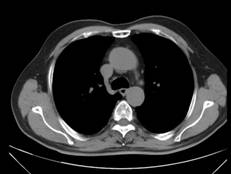

杨××,男,63岁,CT示右肺门占位(图1a~b)经穿刺活检证实右肺门部腺癌、纵膈淋巴结转移,基因检测提示“吉西他滨、5-Fu、铂类”化疗药物敏感;经三次介入治疗后CT(2012年12月19日)复查,瘤体明显缩小,纵膈肿大淋巴结消失(图2a~b);后无特殊治疗,4年后复查(2017年1月8日),病情稳定,瘤体不明显(图3a~b)。

图1a 图1b

图2a 图2b

图3a 图3b